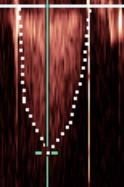

# of Biologic Valves 生物瓣

Examples of (A) stented, (B) stentless, and (C) percutaneous biologic valves and their echocardiographic features in diastole (middle) and in systole (right) as seen by transesophageal echocardiography. [2]

经食道超声心动图显示 (A) 有支架、(B) 无支架和 (C) 经皮生物瓣膜及其舒张期 (中) 和收缩期 (右) 的超声心动图特征。

The stentless valve is inserted by the root inclusion technique.

无支架瓣膜是通过根部包裹技术植入的。

Mild perivalvular aortic regurgitation in the percutaneous valve is shown by the arrow.

箭头所示为经皮瓣膜轻度主动脉瓣周反流。